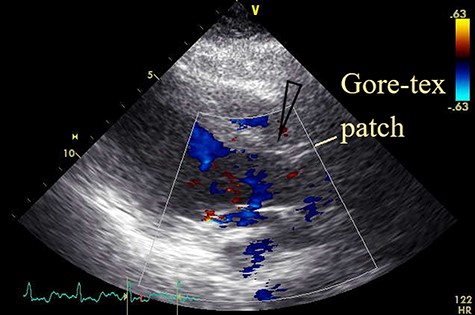

An electrocardiogram showed sinus tachycardia and ST depression in leads V4-V6. A chest X-ray revealed severe lung congestion and cardiomegaly. Transthoracic echocardiography (TTE) showed a ruptured SVA connecting to the right ventricle (RV), a subarterial VSD measuring 10 × 12 mm, with a left ventricular ejection fraction of 47% and normal valve function with mild tricuspid regurgitation (Fig. 1). No clot or vegetation was observed. Blood tests revealed a white blood cell count of 31 000/L, serum creatinine of 321 μmol/L, aspartate aminotransferase of 5199 U/L and alanine aminotransferase of 3458 U/L. The patient was diagnosed with ruptured SVA with VSD in cardiogenic shock and transferred to our hospital for further management.

Preoperative transthoracic echocardiogram. Shunt flow (arrow) from aorta to RV.